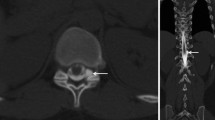

In all patients the density in the renal pelvis, the vena cava (either inferior or superior), and the aorta was measured in Hounsfield units (HU) by one reader (L.B.), on 1‑mm slices with soft tissue kernel in the axial plane using a circular region of interest tool (Fig. 2). In patients with delayed images, the measurements were repeated. In all patients, the GFR (in ml/min) was estimated. The findings were reported in a standardized spreadsheet.

Transversal PMCT after previous intrathecal contrast agent application in a 55-year-old patient with orthostatic headache without epidural CSF collection (SLEC(−)) demonstrating opacification of the renal pelvis and a density measurement using a circular ROI with a mean of 64 Hounsfield units. CSF cerebrospinal fluid, PMCT postmyelography computed tomography, ROI region of interest